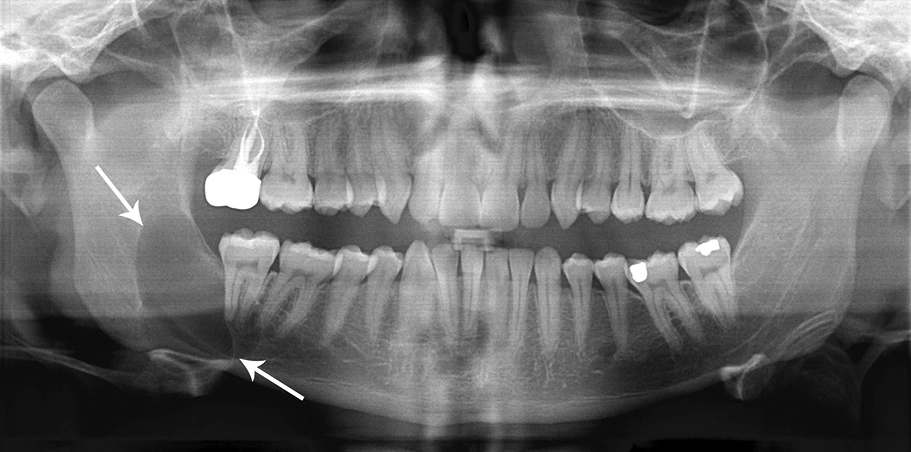

Radiographic Findings

• Appear as well-defined radiolucent areas, mostly unilocular with smooth borders, but multi-locular cysts are also observed.

• Usually the radiolucency is hazy due to keratin filled cavity and is surrounded by thin sclerotic margin due to reactive osteocytes.

• There is extensive spread of the lesion along the medullary cavity with minimal bone expansion, tooth displacement, root resorption or displacement of inferior alveolar nerve. This does not occur until the whole medulla is involved.

• Description : Classic look to a keratocyctic odontogenic tumor in the right mandible in the place of a former wisdom tooth. Unicystic lesion growing along the bone. Lesion was seen by oral surgeon on routine panoramic radiography without any symptoms.